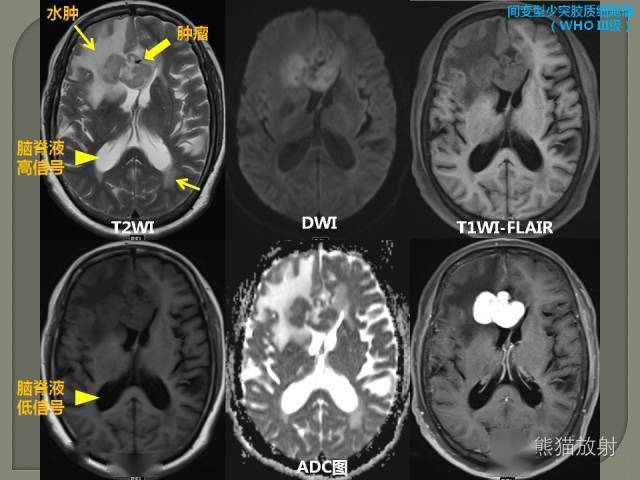

较高的质子密度和非常短的t1值, t1wi,t2wi和pdwi图像上均呈高信号

ir脉冲序列:flair flair用于t2wi和pdwi中抑制脑脊液的高信号,使